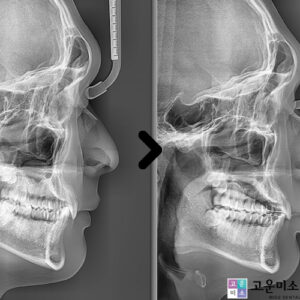

목동치아교정 20년간 한자리를 지켜온 실력으로, 평생 주치의가 되겠습니다.

목동치아교정 만약 부정교합이나 돌출입, 덧니 등의 문제를 겪고 있다면, 미적인 면뿐만 아니라 기능적인 측면에서도 어려움이 생길 수 있습니다. 고르지 않은 치열은 음식물 제거가 어려워 구강 위생을 유지하기 힘들고, 이로 인해 충치가 발생할 확률이 높습니다.   또한 저작능력의 저하와 발음이 부자연스러워지는 불편함이 있을 수 있습니다. 주걱턱, 무턱, 돌출입 등 다양한 원인으로 더보기…

목동교정치과 주치의가 바뀌지 않습니다

목동교정치과, 치아의 배열이 고르지 않거나 모양에 불만을 가지시는 분들이 많습니다. 체중이 늘면 운동이나 식이요법 등으로 관리할 수 있지만, 치아는 마음만으로 교정되지 않죠. 그래서 많은 분들이 치과를 찾아 교정을 통해 원하는 치열을 갖게 됩니다. ​ 치아는 마음대로 변화하기 어려운 신체 부위이기 때문에, 고민이 생기면 전문가의 상담을 통해 본인의 치아 상태를 정확히 더보기…